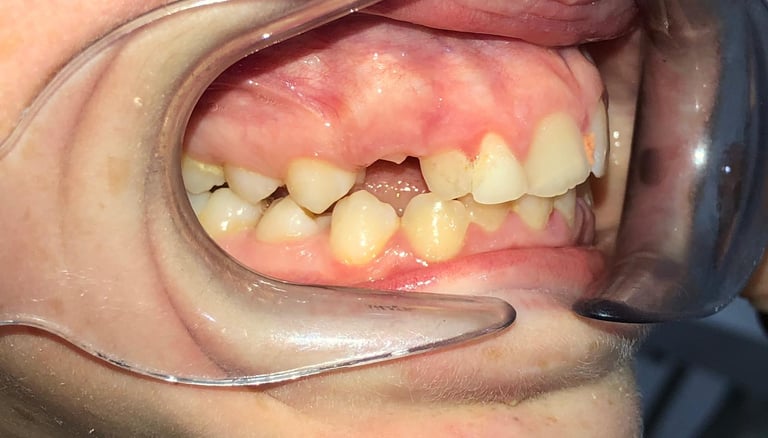

NUESTROS CASOS REALES